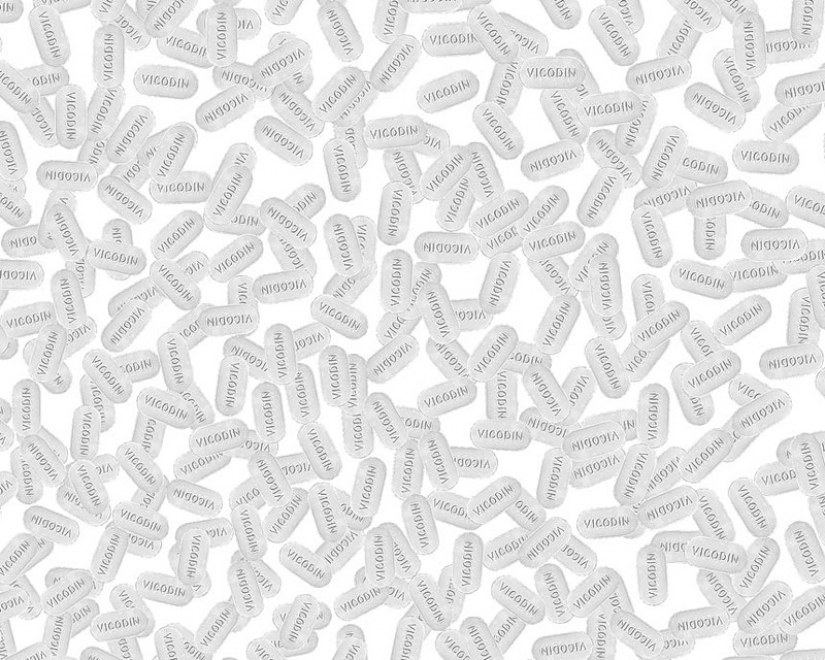

31. 213 thousand tablets of the narcotic painkiller Vicodin (known for the TV series "Dr. house") – is equal to the number of annual ambulance trips in the US on the challenges associated with the use and abuse of pain relievers.